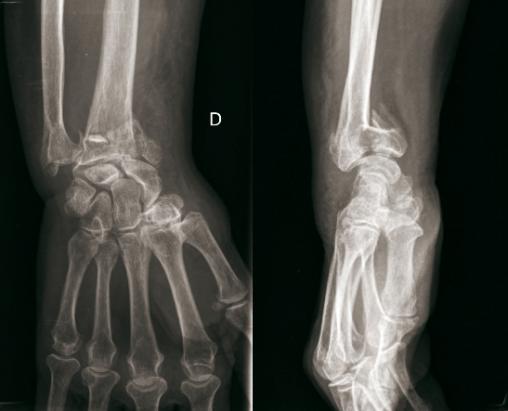

© Henry Coudane, Frédéric Éloy (La Revue du Praticien) Fracture articulaire. (À gauche) Radio de face. (À droite) Radio de profil.